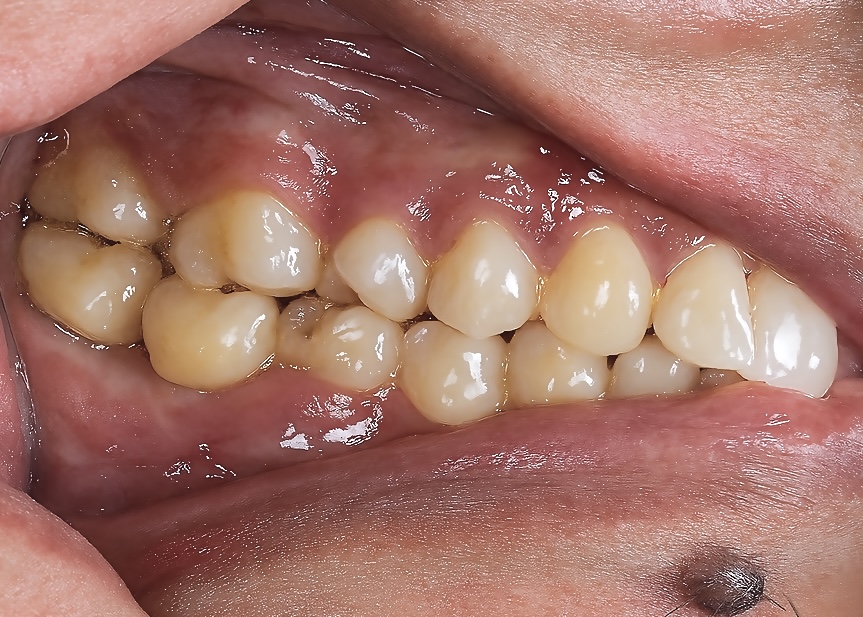

3️⃣ Healing and Soft-Tissue Maturation

After 8 weeks, the peri-implant mucosa showed healthy keratinized tissue with proper emergence form (Fig 2).